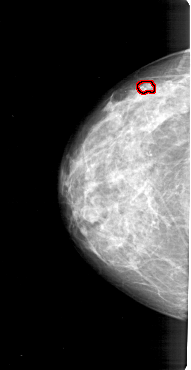

A_1213_1.RIGHT_CC

RIGHT_CC LINES 4711 PIXELS_PER_LINE 2536 BITS_PER_PIXEL 12 RESOLUTION 43.5 NON_OVERLAY

FILE: A_1213_1.LEFT_CC.OVERLAY

TOTAL_ABNORMALITIES 1

ABNORMALITY 1

LESION_TYPE CALCIFICATION TYPE PLEOMORPHIC DISTRIBUTION CLUSTERED

ASSESSMENT 4

SUBTLETY 4

PATHOLOGY MALIGNANT

TOTAL_OUTLINES 1

BOUNDARY